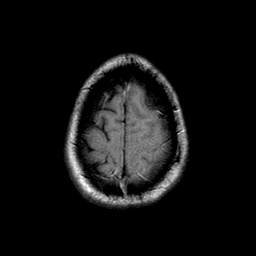

Sarcoma, MR Study #1 mr-t1 -- Slice #22

[Home][Help][Clinical] Slice 22